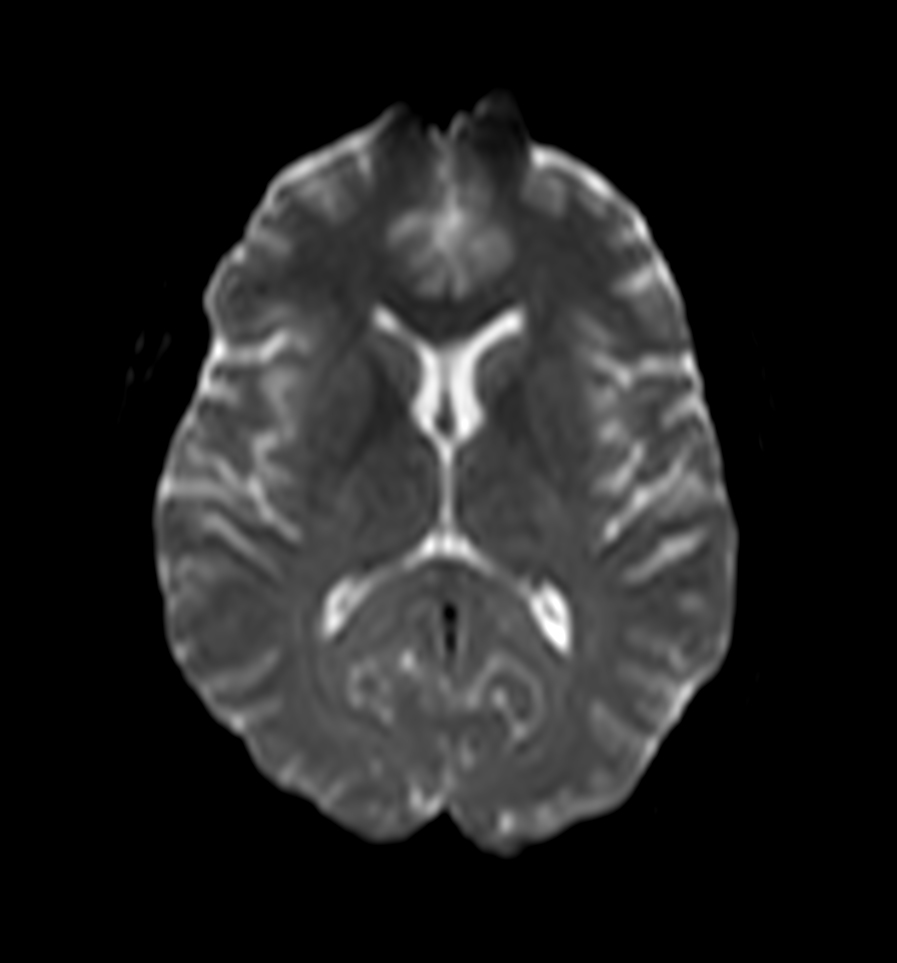

Axial DWI (b0)

Axial DWI (b1000)

Axial DWI (ADC)